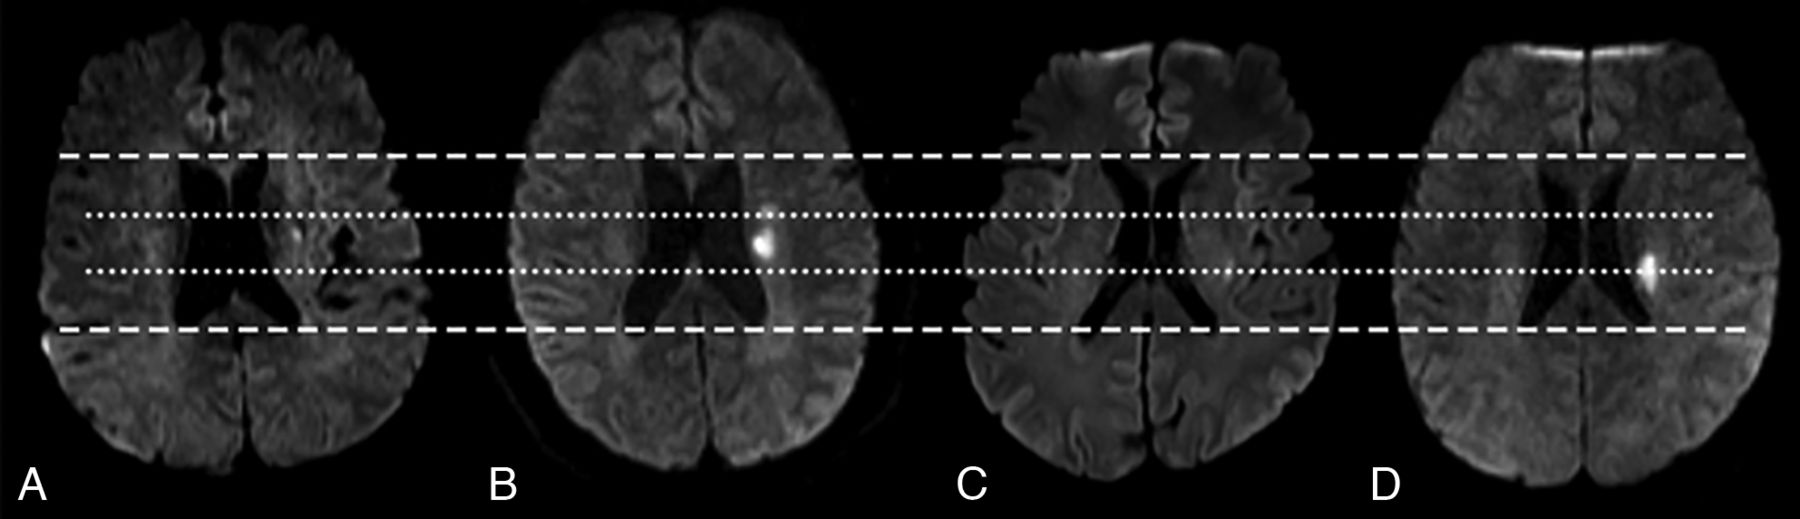

The restricted cubic spline curve showed that the risk of END increased with an increase in the posteriority and laterality indexes (Fig 4). After the receiver operating characteristic curve analysis, the optimal cutoff points of the posteriority and laterality indexes for predicting END were determined (0.669, 0.950)(Online Supplemental Data), and these cutoff values were used to divide the lenticulostriate SSSIs into 4 types: anterior lateral type (AL-type), anterior medial type (AM-type), posterior lateral type (PL-type), and posterior medial type (PM-type) (Fig 5). After the multivariate analysis, in comparison with the AL-type, the AM-type (OR: 3.26; 95% CI: 1.10–9.65), PL-type (OR: 4.68; 95% CI: 1.41–15.56), and PM-type (OR: 6.77; 95% CI: 2.53–18.04) showed significantly elevated risks of END. The PM-type had the highest risk of END (Fig 6).

Lesion location types (A) anterior lateral type (AL-type, posteriority index <0.669 and laterality index <0.950); (B) anterior medial type (AM-type, posteriority index <0.669 and laterality index ≥0.950); (C) posterior lateral type (PL-type, posteriority index ≥0.669 and laterality index <0.950); (D) posterior medial type (PM-type, posteriority index ≥0.669 and laterality index ≥0.950).

Our results have several notable clinical implications. Our study provides a novel and reliable imaging marker for predicting END in patients with lenticulostriate SSSIs. Physicians should pay more attention to patients with PM-type lesions, which carry the highest risk for END. For clinical user convenience, PM-type lesions can be considered as lesions located at the posterior one-third of d1 and adjacent to the lateral ventricle, as shown in Fig 5. Once high-risk patients are identified, earlier doctor-patient communication may prevent potential medical disputes. More aggressive treatment strategies should be considered to eliminate upcoming progress.